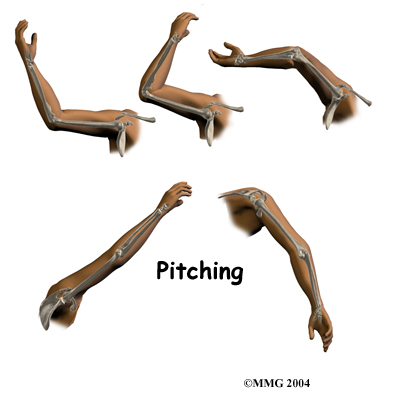

For example, pitching can lead to an overuse strain and, in turn, cause elbow OCD. Throwing puts a lot of force on the elbow joint, and when this action is repeated frequently, it can damage the immature joint surface of an adolescent's elbow. After winding up and bending the arm back, the pitcher must quickly accelerate the arm to gain ball speed. However, the pitcher also has to almost immediately slow the arm down and follow through with the throw. In addition, the pitcher may angle the elbow outward slightly during the acceleration phase to get more ball speed. This action wedges the head of the radius against the capitellum. Furthermore, as the pitcher slows the arm down during the follow-through after a pitch, the forearm is fully pronated. This action puts extra pressure on the humeroradial joint.

Similarly, hitting a ball with a racket can strain the elbow in a similar manner as pitching a baseball. Gymnasts are also at risk of high forces on the capitellum when they repeatedly perform maneuvers with their hands and elbows locked out straight.

Our physical therapists will also work with you to help improve your form in ways that reduce strain on your elbow during sports. Pitchers and racket-sport players might benefit from keeping the elbow aligned correctly, instead of angled outward, during the acceleration phase of the pitch or swing.